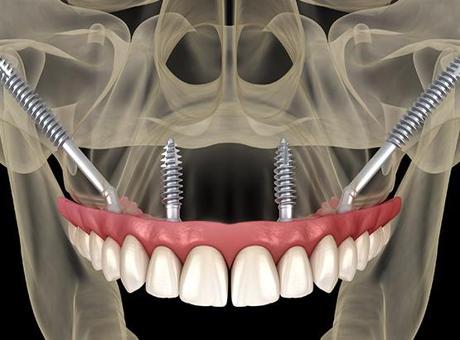

Zigomatik implantlar, üst çene kemiği yetersiz olan hastalarda implantın elmacık kemiğine içten tutundurulmasıyla yapılan özel bir tedavi yöntemidir. Elmacık kemiği çok sağlam olduğu için implantlar burada güçlü bir şekilde tutunur. Bu da hastaya uzun ömürlü ve güvenilir bir çözüm sunar.

En önemli avantajlardan biri süredir. Aylarca kemik oluşmasını beklemek yerine, birçok hastada aynı gün sabit dişlere geçmek mümkün olabilmektedir.

Son yıllarda gelişen dijital planlama ve cerrahi teknikler sayesinde bu implantların yerleştirilmesi hem daha güvenli hem de daha kontrollü hâle gelmiştir. Doğru hasta seçimi ve deneyimli bir ekip ile yapıldığında sonuçlar yüz güldürücü olmaktadır.